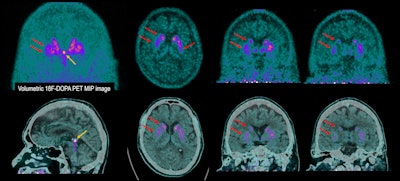

70-year-old man with involuntary movements and tremors in the left lower limb for two years. He also suffered from anxiety and depression. History of treatment with clebopride due to functional gastrointestinal disorders. This dopamine antagonist drug could explain altered movements of pharmacological origin. Brain PET scan with F-18 DOPA shows evident decrease in tracer uptake in both striatum nuclei with right predominance (red arrows), depicting presynaptic dopaminergic deficit of the nigrostriatal pathway, compatible with Parkinson´s disease. (Yellow arrow) Incidental tracer uptake in calcified pituitary gland. (Upper row) PET images. (Lower row) Fused PET/CT images.